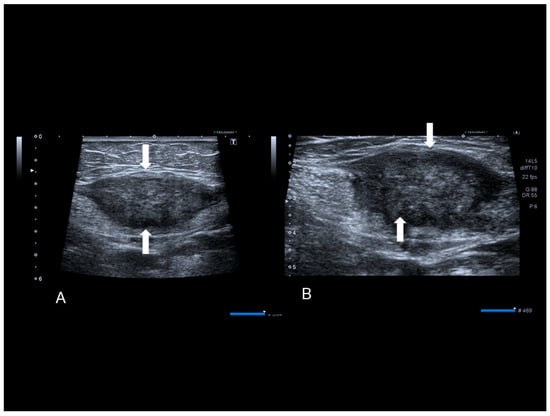

Figure 1. Ultrasonographic images of two nodules (AC) (see white arrows), of scar endometriosis with some color spots (C) due to internal vascularization, infiltrating the external oblique muscle in a woman with a previous cesarean section some years before. Drawing of the location (D).

Scar endometriosis may present as a hypoechoic solid nodule with hyperechoic spots or strands which represent fibrosis within the scar tissue, a hyperechoic peripheral ring, spiculated borders and a single vessel entering the nodule from the periphery (Figure 1 and Figure 2) [11,12,13]. In nodules larger than 30 mm, cystic portions and/or fistulous tract, loss of oval or round shape, multiple vascular pedicles, and central vascularization are more frequent [12].